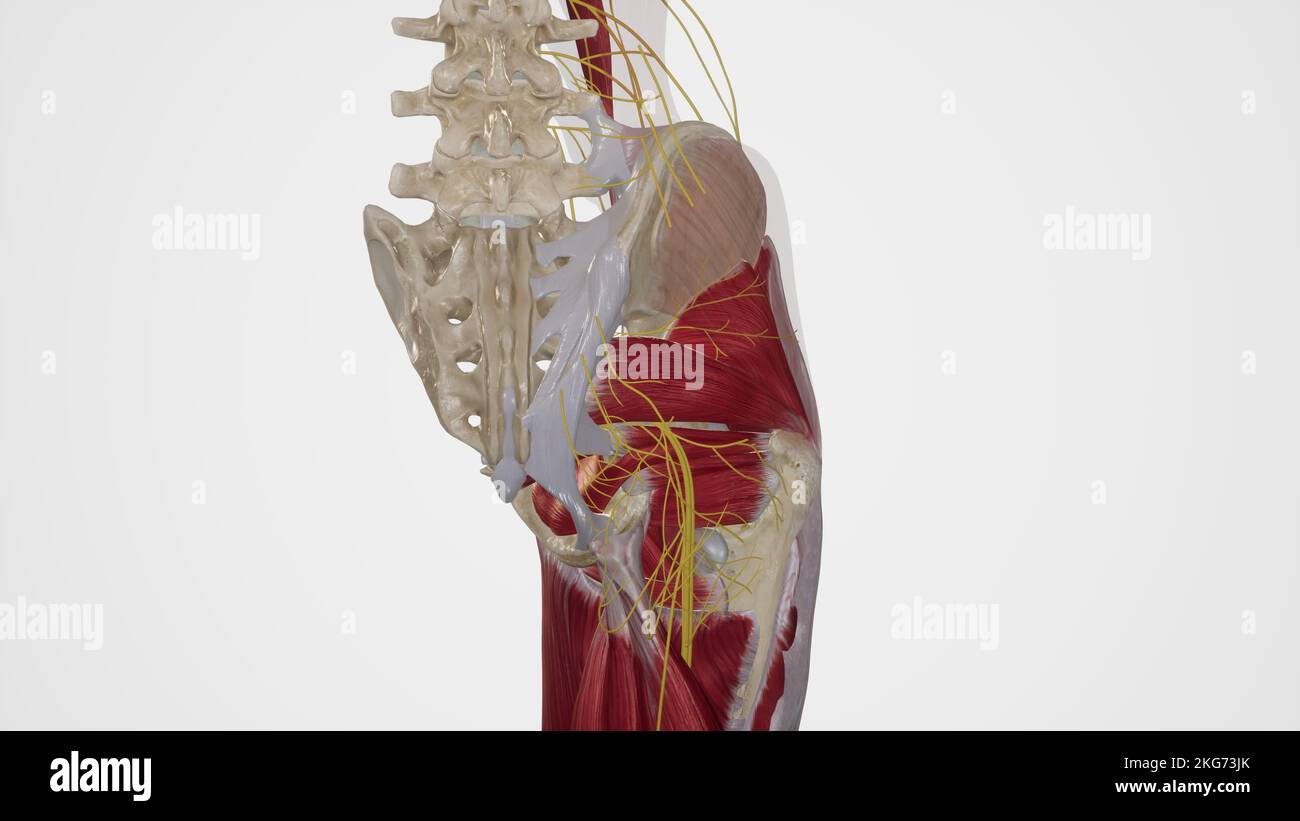

Nerves of Gluteal Region Stock Photohttps://www.alamy.com/image-license-details/?v=1https://www.alamy.com/nerves-of-gluteal-region-image491881339.html

Nerves of Gluteal Region Stock Photohttps://www.alamy.com/image-license-details/?v=1https://www.alamy.com/nerves-of-gluteal-region-image491881339.htmlRF2KG73JK–Nerves of Gluteal Region